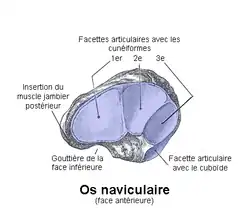

Os naviculaire

Description

C'est un os étroit d'avant en arrière, allongé transversalement, à grand axe oblique en bas et en dedans.

De forme grossièrement parallélépipédique, on lui décrit traditionnellement six faces (quelquefois quatre faces et deux extrémités) :

Face supérieure

La face supérieure est convexe.

Face inférieure

La face inférieure est concave et présente une gouttière pour le muscle tibial postérieur.

Face postérieure

La face postérieure est concave dans tous les sens et forme une surface articulaire qui répond à la facette articulaire naviculaire du talus. L'articulation formée contribue à l'articulation talo-calcanéo-naviculaire.

Elle donne attache au ligament calcanéo-naviculaire à son extrémité latérale et au ligament talo-naviculaire.

Face antérieure

La face antérieure est plane et s'articule avec les trois os cunéiformes pour former l'articulation cunéo-naviculaire.

Face latérale

La face latérale ou extrémité latérale. Elle repose sur le cuboïde et s'articule avec la face médiale du cuboïde.

Face médiale

La face médiale ou extrémité médiale est très réduite et présente une éminence arrondie : la tubérosité de l'os naviculaire (ou tubercule du scaphoïde). Elle sert de point d'insertion pour le muscle tibial postérieur et pour le ligament cunéo-naviculaire médial.